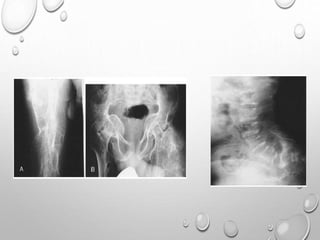

• 1. DYSPLASTIC OR SQUARE

ILIAC BONES

2. NARROW SACRO-SCIATIC

NOTCHES

3. FLAT BILATERAL

ACETABULAR ROOFS

4. SHORT BOTH FEMORAL

NECKS

5. CHAMPAGNE GLASS-

SHAPED PELVIC CAVITY